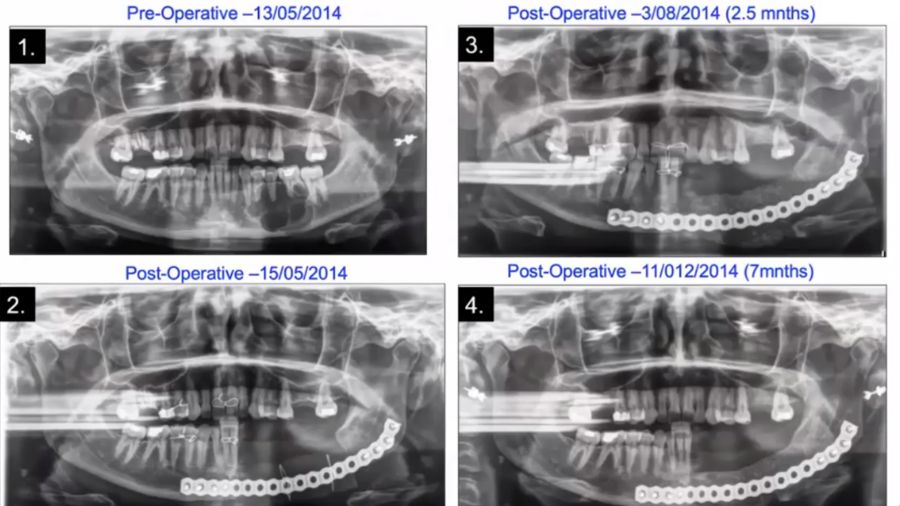

This case with Professor Carlo Ferretti involved a patient with ameloblastoma, which required resection and reconstruction. Virtual treatment planning was very beneficial in this case, allowing us to bend the plate on a 3D model and develop cutting guides for the patient-matched plate. We removed the tumor intraorally—so no incision on the outside—and inserted the plate, followed by a silastic spacer.

The spacer was placed in very much the same anatomy as the resected jaw, obviously without the tumor, and held in position with wire.

After closing the defect, the spacer remained in place for three months, after which time it was removed via an extraoral incision. The nice thing about silastic is that it’s like rubber, so when you have to remove it, it slips out beautifully. We removed the soft tissue from the proximal and distal stumps then in the pocket left behind we were able to inject compressed particulate cortico-cancellous iliac crest bone.

The final reconstruction involved placing implants in the graft, a procedure that was executed very effectively and accurately with assistance from virtual treatment planning.